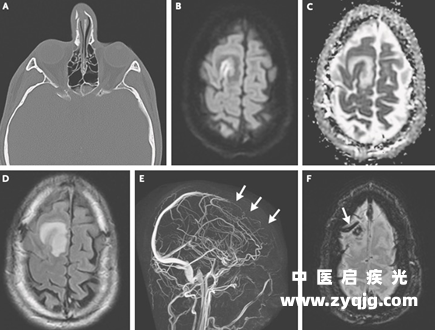

虽然初步的神经系统体格检查并无异常,但阿峰的脑核磁结果却明确显示上矢状窦前部和右额叶凸面皮质静脉各有一枚血栓,右额上回皮层和右额叶白质出现了明显水肿

1.png

图源:参考资料 15

这极有可能就是他反复癫痫发作的原因。